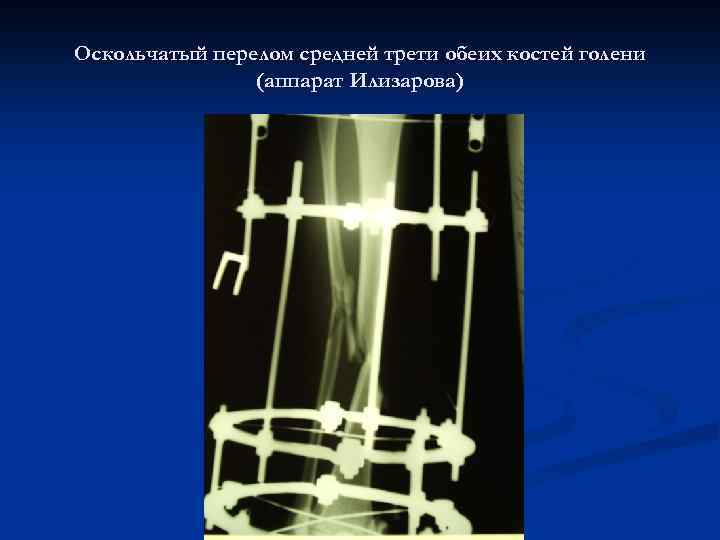

Оскольчатый перелом средней трети обеих костей голени (аппарат Илизарова)

Оскольчатый перелом средней трети обеих костей голени